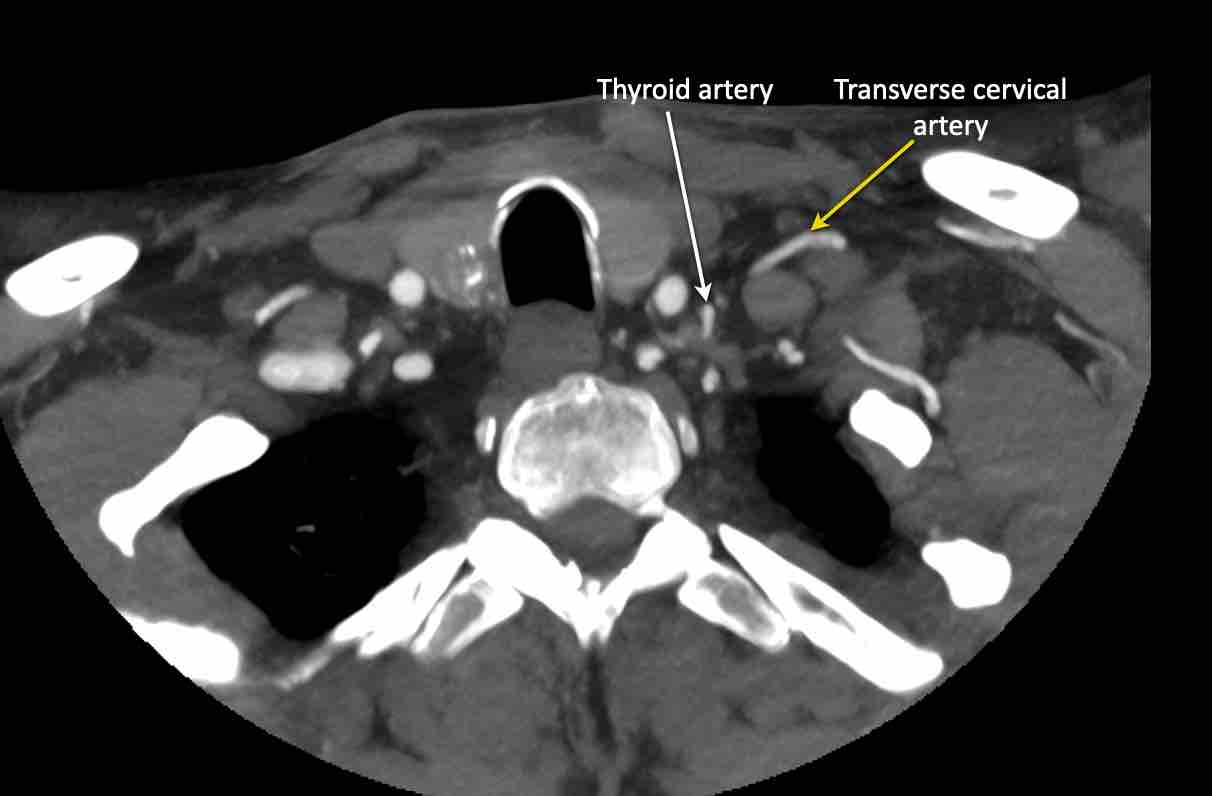

Động mạch cổ ngang

Cuộn qua các hình ảnh để xem giải phẫu của động mạch cổ ngang.